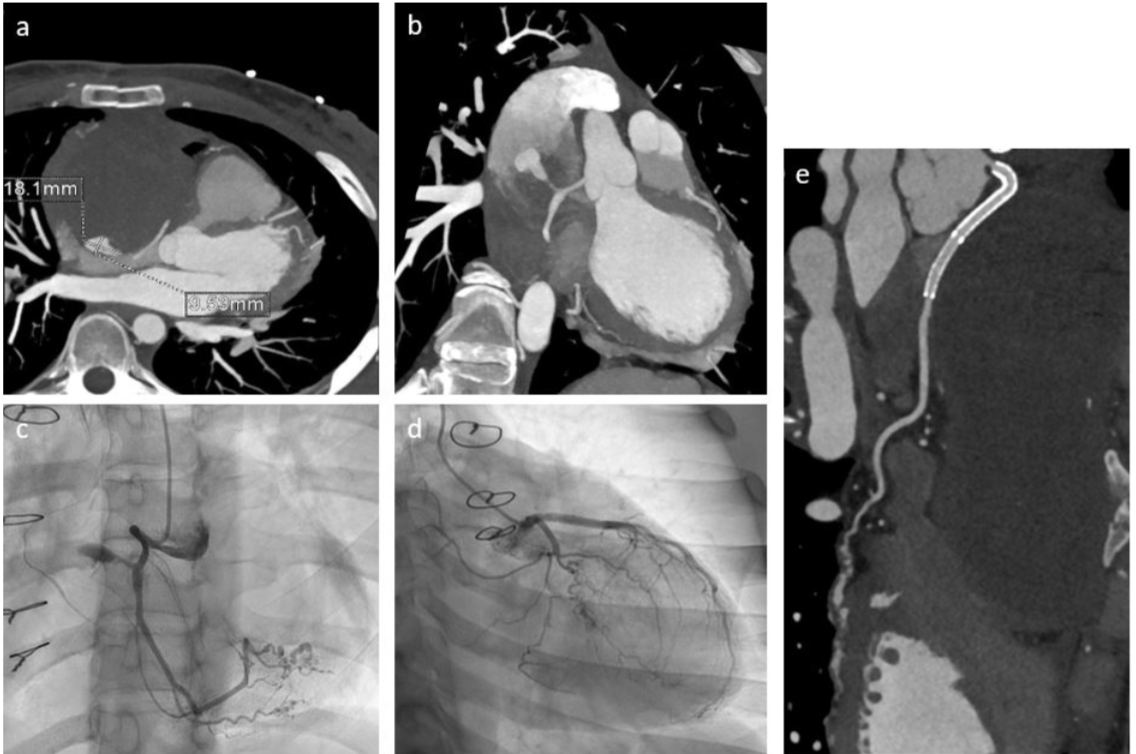

Axial (a) and coronal (b) MIP reformat images from CCT show a focal area of enhancement within the peripheric portion of the lesion, communicating with the right coronary artery trough a slender acute marginal branch/atrial branch; the same finding is confirmed by invasive coronary angiography (c-d) which also shows multiple stenosis with ectasia of intervening tracts of the right postero-lateral branch, the distal portion of posterior descending artery, and an obtuse marginal branch of LCX. Follow-up CTA after PCI shows patency of the overlapping stents in the proximal tract of RCA, with complete exclusion of the pseudoaneurysm.